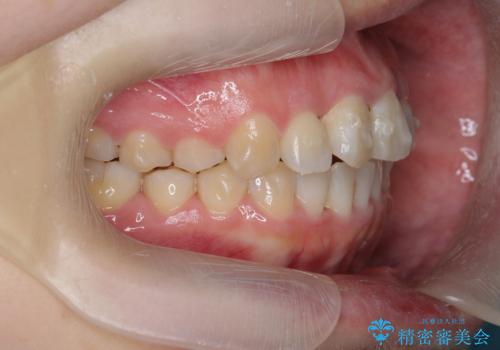

- 前歯のねじれを改善したい、と矯正治療を希望され来院されました。

上下の歯のがたつきを改善するマウスピース矯正治療と、下顎に見られる大きな骨隆起を外科的に除去する治療計画を進めていきます。

歯並びが改善したとともに、骨隆起を除去したことで舌をしまうスペースも増え安定した口腔内環境を確立することができました。